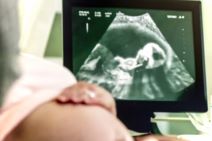

AKO VAS ZBUNJUJE ULTRAZVUČNA SLIKA VAŠE BEBE: Kratki vodič kroz najvažnije kratice važnog trudničkog nalaza